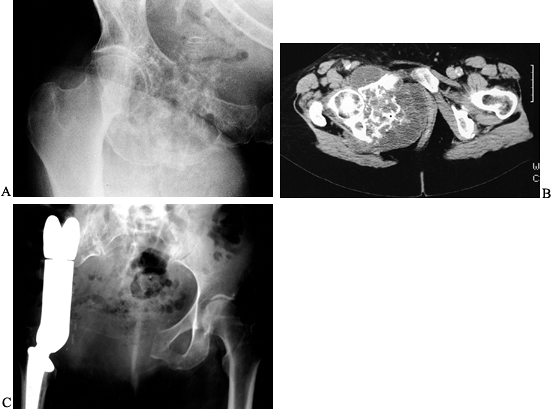

![]() |

|

Figure 126.14. A: AP radiograph of the distal femur in a 24-year-old man. A low-grade osteosarcoma is present in the distal femur. B: Lateral radiograph. Note the marked bone destruction. C: MRI scan, coronal image (T1-weighted). The tumor involves the lower end of the femur. D:

AP radiograph after resection of the distal femur (intra- articular). The knee is reconstructed with an allograft and rotating hinge knee prosthesis. E: Lateral radiograph of knee reconstruction. |